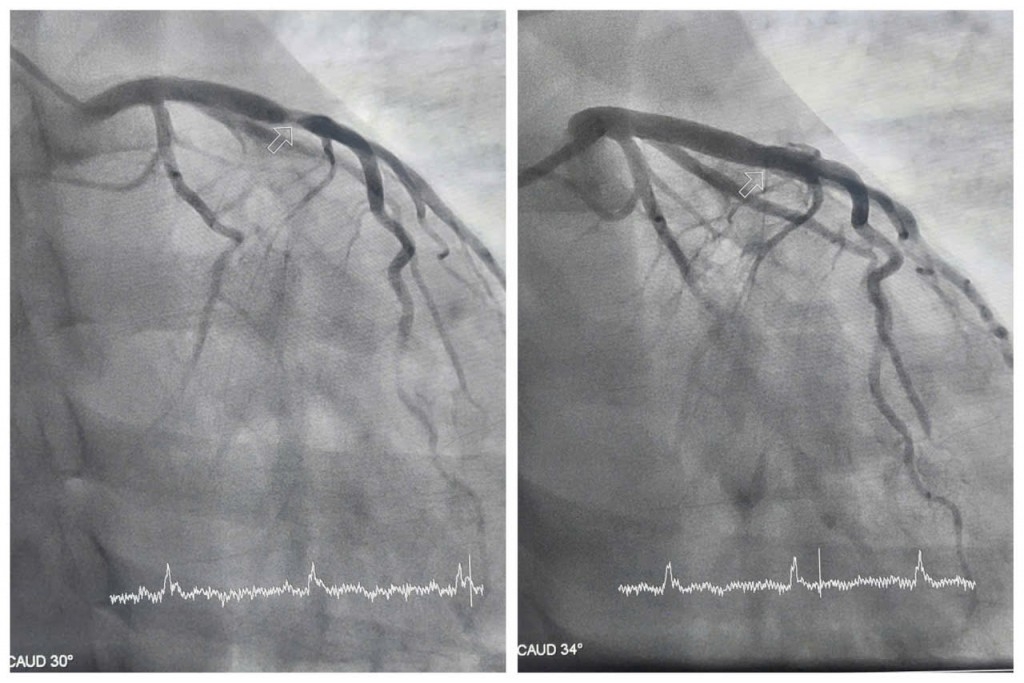

Kết quả chụp mạch vành cho thấy động mạch liên thất trước – một trong những nhánh quan trọng nhất nuôi dưỡng cơ tim bị tổn thương nặng, hẹp khít tới 99%. Trước tình huống nguy kịch, các bác sĩ khoa Phẫu thuật và Can thiệp Tim mạch đã nhanh chóng đặt stent nhằm tái thông máu nuôi tim, giúp người bệnh thoát khỏi tình trạng nguy hiểm.

Nhờ được phát hiện sớm và xử trí kịp thời, ca can thiệp diễn ra thuận lợi. Bệnh nhân H. hồi phục nhanh, không đau tức ngực, các chỉ số tim mạch dần ổn định. BS.CKII Trần Quang Định, Trưởng khoa Phẫu thuật và Can thiệp Tim mạch, Bệnh viện Đa khoa tỉnh Quảng Ninh, cho biết: "Đây là ca nhồi máu cơ tim trẻ nhất từ trước đến nay mà khoa tiếp nhận điều trị".